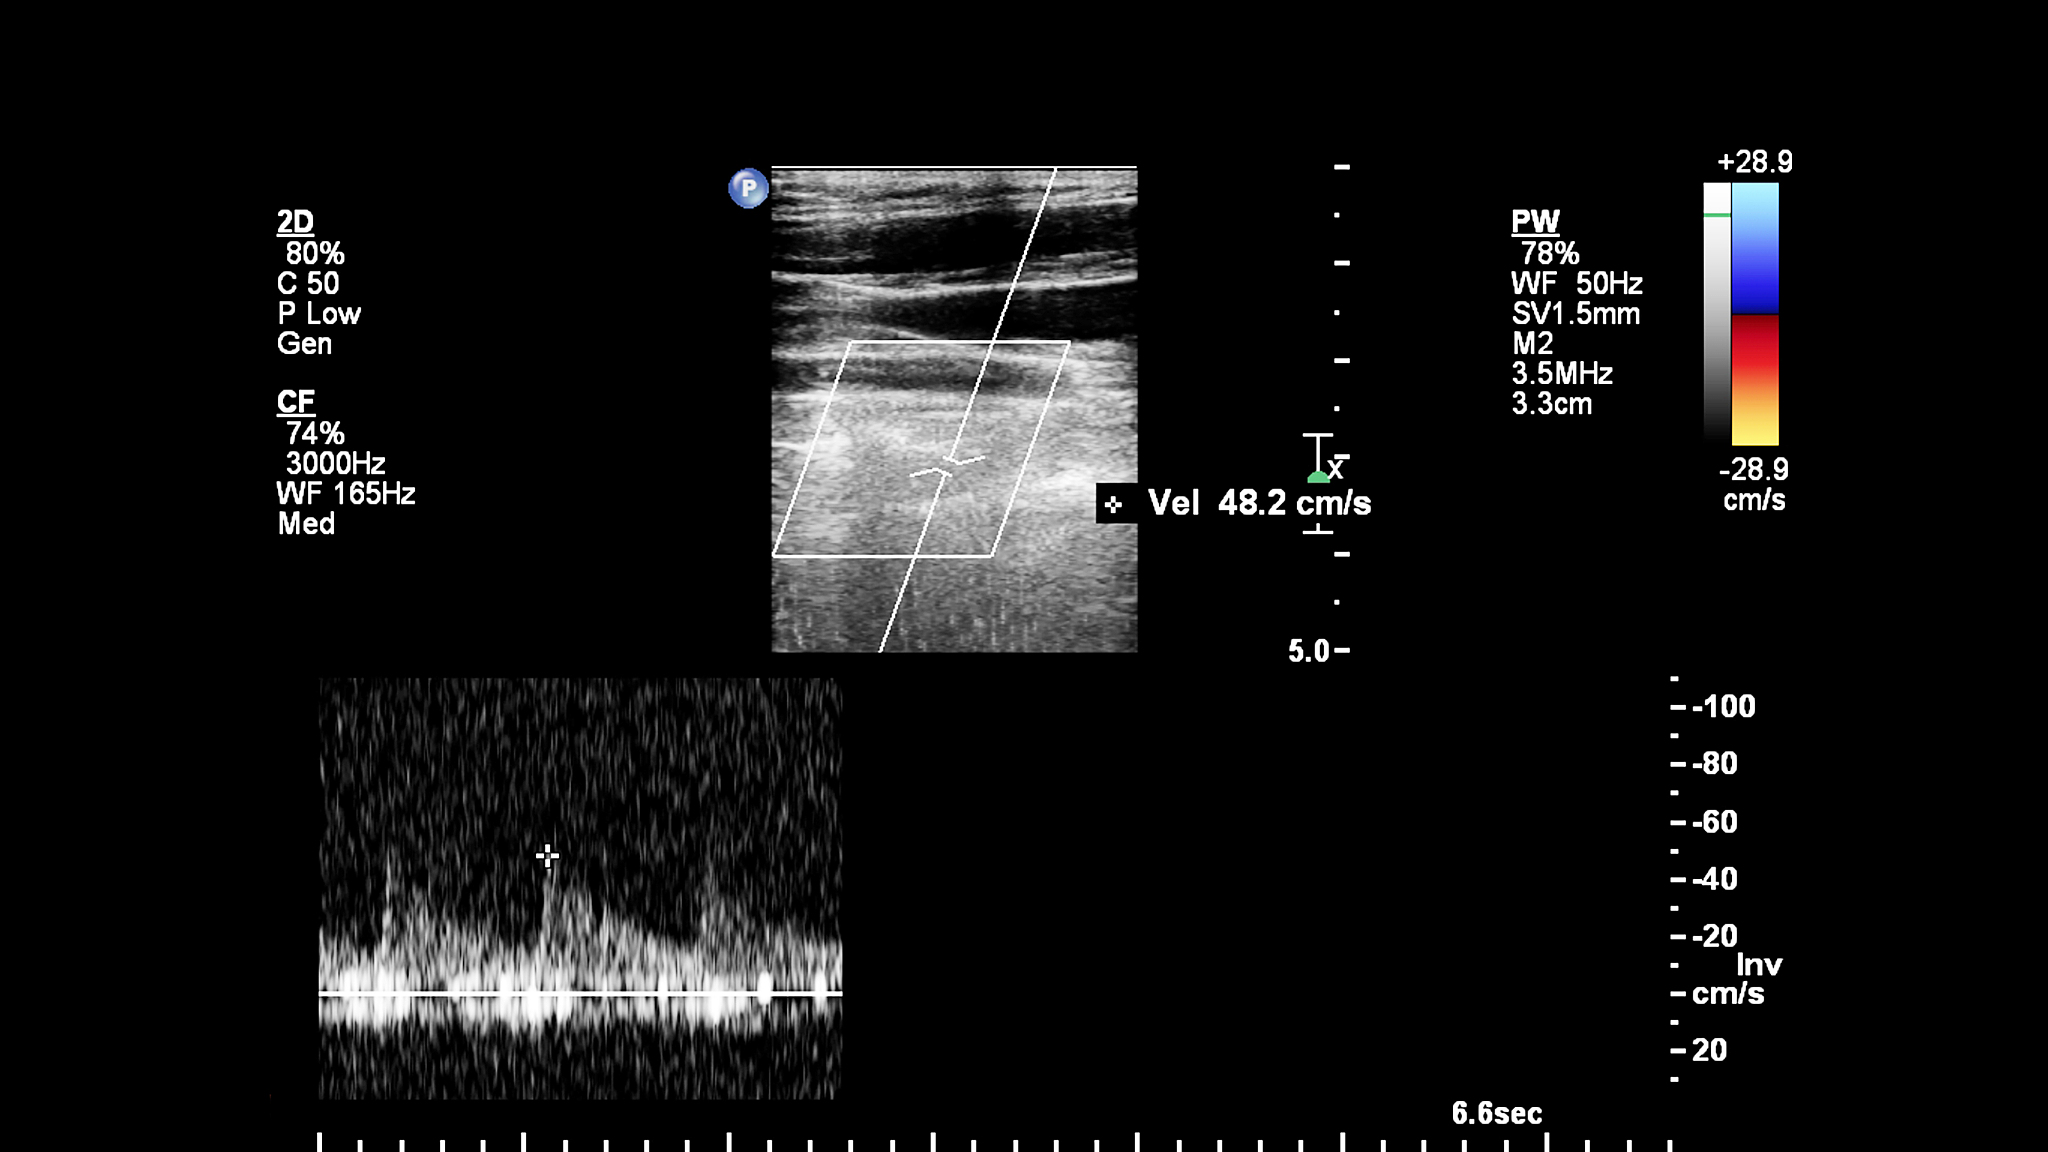

血管内超声诊断(Intravascular ultrasound,IVUS)是一种常见的介入性心血管诊断技术,可以提供高分辨率的血管壁结构和血流动力学信息。IVUS探头是通过导管插入血管内进行操作的,但是传统的IVUS探头在插入导管时需要使用快速交换接头,而且探头显影性较差,这些问题限制了IVUS技术的应用和发展。